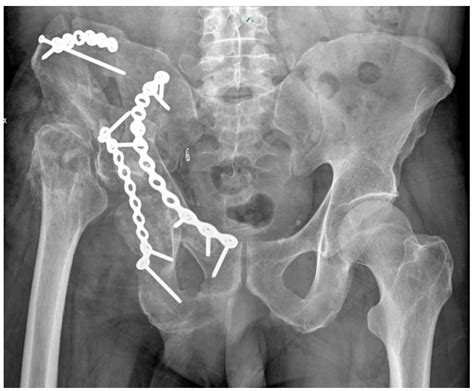

Open Reduction and Internal Fixation (ORIF) is the standard surgical approach for Fractures Of Acetabulum. The objective is to restore the smoothness of the joint surface and the stability of the pelvic ring. Surgeons use plates and screws to hold the bone fragments in place, allowing for earlier mobilization and a better long-term functional outcome.

💡 Note: Patients undergoing ORIF must strictly adhere to weight-bearing restrictions provided by their orthopedic surgeon, as premature loading can lead to hardware failure or secondary displacement of the fracture.